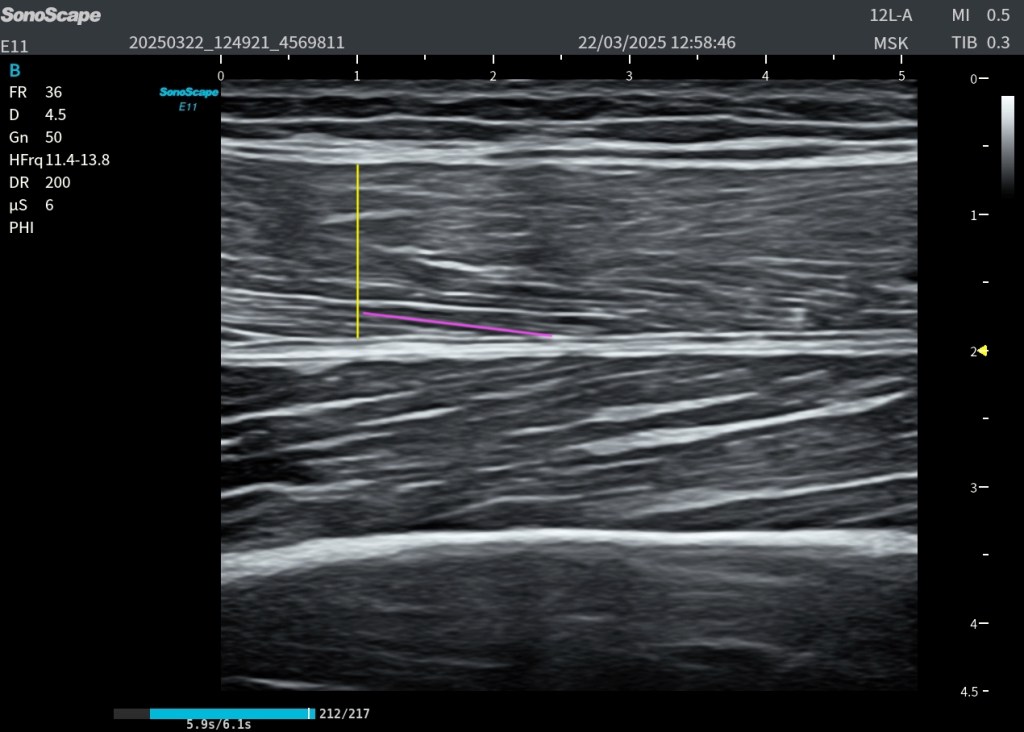

En esta imagen 1 se aprecia de forma muy clara la anatomía en un corte axial oblicuo del tercio medio del cuello anterolateral, una de las ventanas más útiles para el estudio ecográfico del plexo braquial.

En la porción medial identificamos el paquete vascular principal, formado por la arteria carótida y la vena yugular interna, que actúan como referencias anatómicas fundamentales. En un plano más superficial se observa el músculo esternocleidomastoideo, y aún más superficial, el músculo platisma.

Por debajo del esternocleidomastoideo y desplazándonos hacia lateral, aparece el músculo escaleno anterior, que constituye uno de los límites del espacio interescalénico.

Entre el escaleno anterior (medial) y el escaleno medio (lateral) se localiza el plexo braquial, en este nivel formado fundamentalmente por raíces y troncos, no por ramas terminales. Estas estructuras nerviosas presentan en ecografía un aspecto característico, ligeramente hipoecoico, con patrón fascicular, a menudo descrito como “racimo de uvas”.

Más lateral se identifica el músculo escaleno medio, y posteriormente el escaleno posterior, completando el grupo muscular profundo del cuello en esta región.

En el plano más profundo y lateral, se puede reconocer la primera costilla, que actúa como referencia anatómica clave y como límite posterior del espacio donde discurre el plexo.

En la imagen 2 observamos un corte axial más lateral del cuello anterolateral, donde la anatomía del plexo braquial se representa de forma muy clara y didáctica.

En este plano se identifican cinco estructuras clave que debemos reconocer con precisión:

En primer lugar, el grupo de los músculos escalenos, delimitados mediante líneas punteadas de colores:

El escaleno anterior, marcado en línea punteada amarilla (más medial)

El escaleno medio, marcado en línea punteada azul (más lateral y principal referencia junto al anterior)

El escaleno posterior, marcado en línea punteada morada (más posterior)

Entre el escaleno anterior y el escaleno medio se localiza el plexo braquial, que en este nivel corresponde a raíces y troncos. Es fundamental entender que aquí no estamos viendo ramas terminales, sino la porción proximal del plexo.

El plexo aparece representado en color naranja, mostrando sus tres componentes principales: tronco superior, medio e inferior, con el aspecto ecográfico típico ligeramente hipoecoico y fascicular, en forma de “racimo de uvas” o gominola de mora.

Estos dos músculos escalenos anterior y medio, actúan como un auténtico marco protector anatómico, delimitando el espacio donde discurre esta estructura nerviosa tan relevante como es el plexo braquial.

Es fundamental recordar que existe variabilidad anatómica, incluso entre ambos lados del mismo paciente, lo que obliga a interpretar siempre la imagen en su contexto y no de forma rígida.

Como referencia profunda y lateral, se identifica la primera costilla, representada en color verde, que sirve como punto de orientación anatómica clave.

En ecografía, esta zona es especialmente agradecida porque combina músculo, nervio y vasos en un mismo campo. Los escalenos muestran su patrón muscular habitual, mientras que el plexo aparece como un conjunto de estructuras redondeadas, habitualmente hipoecoicas, con un aspecto fascicular que recuerda a las gominolas de mora o a un patrón en panal de abeja. Técnicamente, los nervios contienen fascículos hipoecoicos rodeados de tejido conectivo hiperecogénico, lo que explica ese patrón mixto tan característico.

Para estudiarlo bien, no basta con verlo en un único corte. Es necesario explorarlo en transversal y en longitudinal.

El corte transversal permite reconocer el plexo entre los escalenos. El corte longitudinal ayuda a seguir las raíces y comprender su continuidad hacia los troncos. Esta maniobra es clave para no confundir el plexo con otras estructuras del cuello.